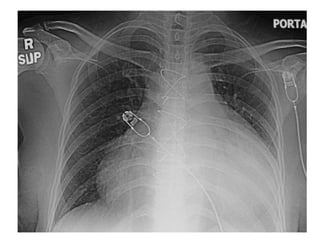

• Pericardial effusion------------

tampnade

• However, patients with a large pericardial

effusion, a hemodynamically significant

pericardial effusion, a suspicion of a

bacterial or neoplastic etiology, or

evidence of constrictive pericarditis

should be evaluated for invasive

therapies, such as pericardial

drainage and/or pericardiotomy.